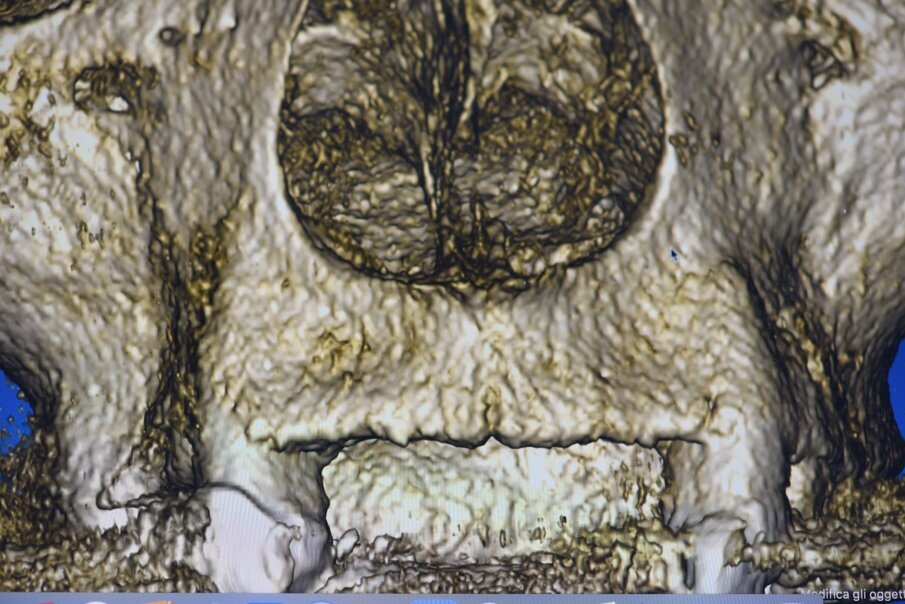

L’informazione diagnostica dettagliata è fornita dalla CBCT, pertanto abbiamo pianificato la sua esecuzione dopo la prima provvisorizzazione dell’arcata superiore evitando lo scattering da metalli presenti. Il file STL del wax-up (Fig. 6) associato al file STL dell’impronta senza provvisorio (Fig. 7) e al file DICOM radiologico (Figg. 8, 9) ha permesso una corretta progettazione chirurgico implantare (Fig. 10) nel rispetto della porzione ossea della cresta residua, ottimizzando la conseguente realizzazione della dima chirurgica (Fig. 11) per il posizionamento degli impianti in sede 1.2 e 2.2 (Figg. 12-14) anche nel rispetto della posizione degli elementi in antagonismo (Fig. 15). Il primo provvisorio avrà diverse funzioni tra cui la valutazione dell’inclinazione coronale, l’ingombro volumetrico e il supporto labiale del gruppo frontale per la correzione dell’emergenza del labbro superiore (Fig. 16). Dopo un breve periodo di stabilizzazione funzionale di almeno due mesi, si valutano i movimenti mandibolari, masticatori, il ripristino dei tessuti parodontali e il condizionamento biologico degli elementi intermedi. Nello specifico del caso trattato abbiamo evidenziato subito un collasso della masticazione associato a un morso profondo che non avrebbe consentito alcuna protesizzazione degli elementi mancanti (Fig. 2). Pertanto abbiamo dovuto realizzare un rialzo di masticazione anche per correggere l’emergenza degli elementi sostitutivi. La preparazione degli elementi residui concepita ha eliminato tutti i materiali che avrebbero creato un disturbo nell’indagine radiologica (Fig. 17).

Fig. 8_Impatto visivo della CBCT nella porzione vestibolare che evidenzia la marcata lacuna ossea che impatta sull’estetica del II° sestante.

La CBCT ha riscontrato un deficit del volume osseo nella porzione vestibolare (Fig. 8), pur mantenendo la possibilità di alloggiare gli impianti in osso nativo e rigenerando la parte vestibolare nell’intento di dar maggior supporto al labbro, in sostituzione della flangia di resina del precedente provvisorio. La dima chirurgica progettata in previsione di un intervento a lembo aperto viene stabilizzata dai diversi monconi presenti sull’arcata preparati evitando sottosquadri e angoli vivi che renderebbero difficoltosa la stabilità della dima nell’atto chirurgico. È altresì importante che gli elementi residui non presentino mobilità al fine di limitarne la precisione (Fig. 18). Nel caso di appoggio ai denti naturali della dima chirurgica è necessario che abbia dei fori in corrispondenza degli elementi così da valutare il corretto posizionamento stessa durante l’intero intervento (Figg. 19, 20). In caso di zone estetiche siamo soliti dare prevalenza all’uso di impianti in Zirconia bifasici (Fig. 21). Gli impianti in Zirconia rappresentano un vantaggio in zone estetiche per il loro caratteristico colore oltre che per la particolare biocompatibilità, è infatti ormai noto la formazione di un creaping epiteliale che favorisce una maggior adesione emodesmosomiale con una stabilità del tessuto connettivo perimplantare migliore rispetto al titanio. L’impianto scelto è un impianto bifasico tissue level a connessione interna che presenta un trattamento di superficie tale da renderlo idrofilo, cioè aumenta la bagnabilità di superficie e conseguentemente ne aumenta la prestazione riducendo i tempi di guarigione ossea primaria (Fig. 22).